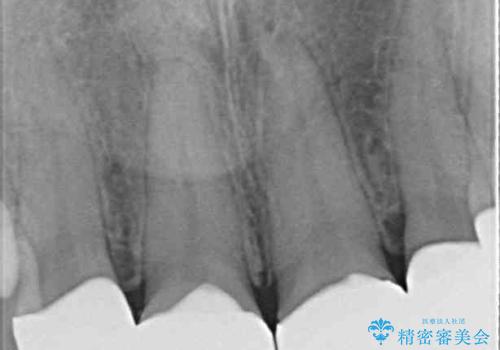

- 前歯の歯並びと虫歯を気にして来院された患者様です。

上下前歯の歯列不正はインビザラインにより歯列を整え、その後に、前歯5本をオールセラミッククラウンにて補綴治療することとしました。

矯正治療前に前歯のむし歯治療を行ったものの、樹脂で充填するには虫歯が広範囲であったため、審美的に問題がありました。

矯正治療にて歯並びを整えた後に、虫歯の大きかった5本の歯をセラミッククラウンにて補綴し、明るい口元になりました。